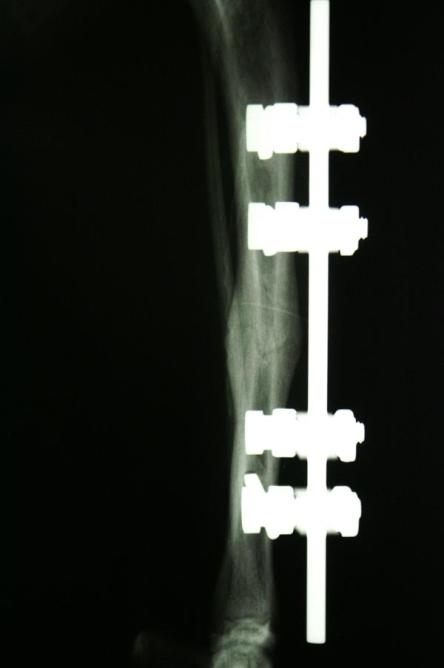

Auf dem Röntgenbild des Beines ist erkennbar, dass das Schienbein in der Mitte quer gebrochen ist. Feine Haarrisse ziehen von der Frakturspalte kniewärts. Das Wadenbein ist intakt, was die relative Stabilität des Bruchs erklärt.

Die Fraktur ist auf Dauer konservativ nicht ausreichend stabilisierbar. Hierzu müsste das Gelenk ober- und unterhalb des Bruchs (d.h. Knie- und Sprunggelenk) immobilisiert werden, was aufgrund der Anatomie eines Katzenbeines nicht möglich ist. Zusammen mit den Besitzern wird entschieden, den Bruch mit einem sogenannten Fixateur Externe zu versorgen.

Nach vier Tagen wird nochmals ein Röntgen des Brustkorbs angefertigt, auf welchem erkennbar ist, dass sowohl Lungenblutung als auch Pneumothorax verheilt sind und eine Narkose somit möglich ist. Je zwei Stahlstifte werden ober- und unterhalb der Bruchstelle durch die Haut in den Knochen gebohrt und ausserhalb des Körpers mittels Klampen, Muttern und einem Verbindungsstift verbunden, was zusammen mit der stabilisierenden Wirkung des Wadenbeins eine ausgezeichnete Fixation ergibt. Der ausserhalb der Haut liegende Teil dieser Konstruktion wird mit einem gepolsterten „Verband“ umgeben, damit die Katze mit den Metallteilen nicht an Gegenständen hängen bleibt.

„Pfüdi“ belastet nach der Operation das Bein sofort wieder sehr gut, muss aber zur besseren Heilung 6 Wochen in seiner Bewegung eingeschränkt werden. Nach dieser Zeit wird ein Röntgenbild angefertigt, welches zeigt, dass die Fraktur sehr gut verheilt ist. Der Fixateur Externe wird in einer kurzen Narkose entfernt.